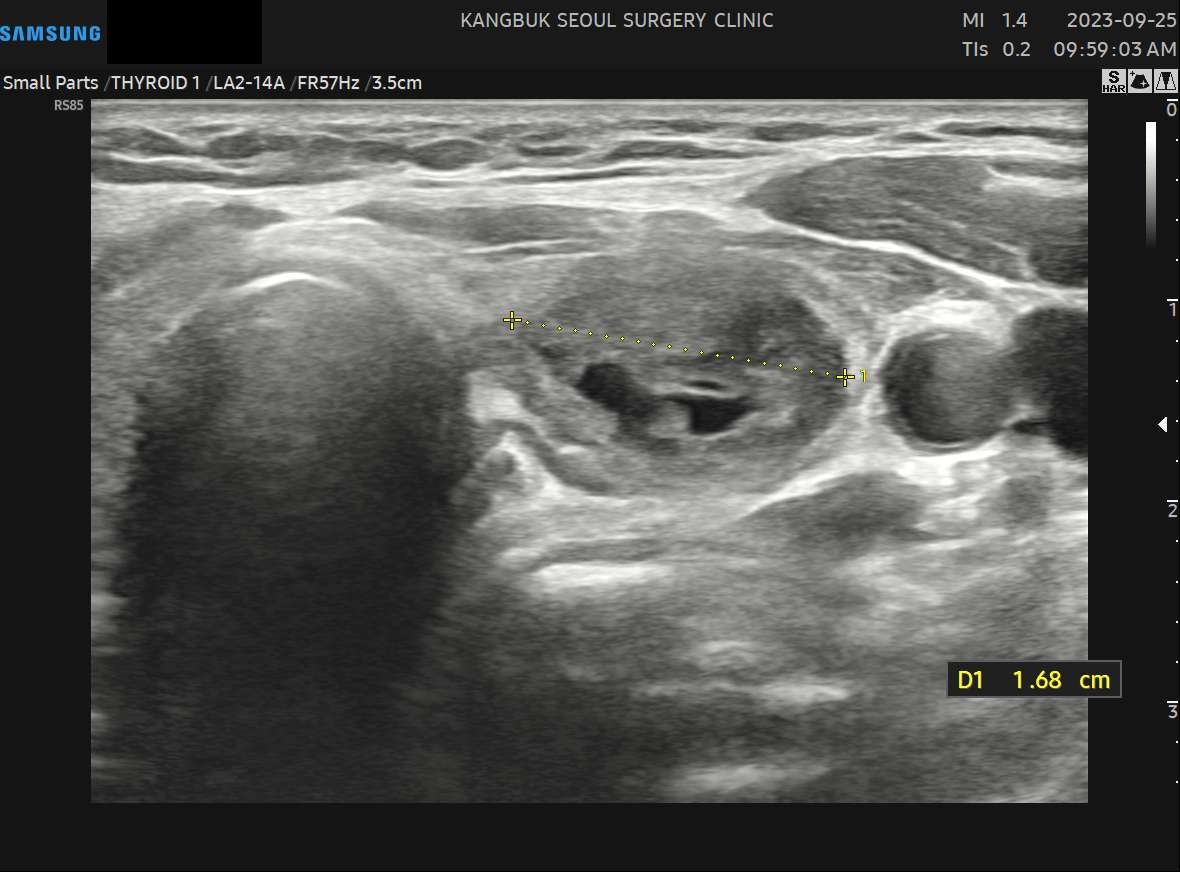

수술 2개월 후(1.68cm)